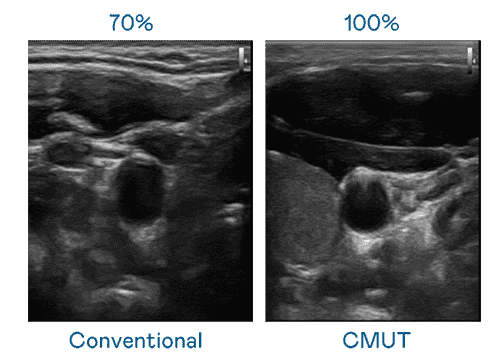

CMUT 技术是一种用电容式微机电元件来产生超音波讯号的技术。。。。与传统 PZT 压电式技术相比,,,,CMUT 频宽增加 30%,,,更宽频的超音波讯号让影像解析度大幅提升,,,是实现高影像品质医疗超音波扫描、、、促进精准医疗发展的关键技术。。

大频宽带来超清晰影像

超音波影像的解析度高低,,,首先取决于探头能发出的讯号频宽。。。赏金国际 CMUT 可提供高清晰的超音波讯号,,,,提供高频宽、、高灵敏度、、、影像纹理细节更高的超音波影像,,协助医护人员缩短影像判读时间及利用精准的医疗影像进行诊断。。